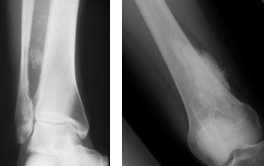

병리적 골절(Pathological fracture)

관련질환

골다공증

,

뼈의 신생물

내연골종

골괴사

피로 골절

골육종